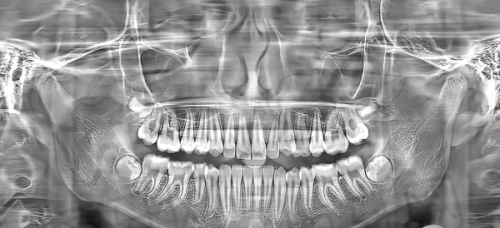

2. **CBCT三维影像设备**:CBCT三维影像设备可以提供口腔内部的三维立体图像,医生可以从多个角度观察牙齿、颌骨等组织的结构和形态。这对于种植牙手术的术前规划、正畸方案的制定等都具有重要的意义。通过CBCT三维影像设备,医生可以更加正确地了解患者的口腔情况,制定出更加科学、合理的治疗方案。